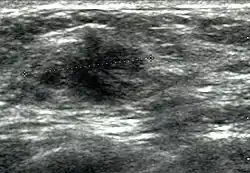

Breast ultrasound is a medical imaging technique that uses medical ultrasonography to perform imaging of the breast. It can be performed for either diagnostic or screening purposes[1] and can be used with or without a mammogram.[2] In particular, breast ultrasound may be useful for younger women who have denser fibrous breast tissue that may make mammograms more challenging to interpret.[3][4]

Elastography is a type of ultrasound examination that measures tissue stiffness and can be used to detect tumours.[7] Breast ultrasound is also used to perform fine-needle aspiration biopsy and ultrasound-guided fine-needle aspiration of breast abscesses.[8]

Breast ultrasound is typically performed using a frequency of 7 to 14 Megahertz, and may also include ultrasound of the axillary tail of the breast and axillae to detect abnormal nodes in the axilla, as lymphatic drainage of parts of the breast occurs through axillary lymph nodes.